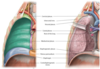

What does the phrenic nerve do?

The phrenic nerves originate from C3-C5 and they innervate the diaphragm. Therefore, they are crucial for breathing.